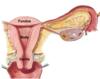

What is the normal anatomical position of the uterus:

anteverted and anteflexed.

- anteverted = angle cervix enters vagina.

- anteflexed = angle between cervix and uterus body.

Anteflexion of uterus:

- angle between cervix and uterus body.

- uterus tipped forward as it rests on the urinary bladder.

Anteversion of uterus:

- angle cervix enters vagina.

- protects/covers external os of cervix.

As the urinary bladder fills in females, what will occur to the uterus?

- retroflexion: uterus body and fundus tips posteriorly.

- retroflex uterus = retrovert cervix angle into vagina.

Label all: